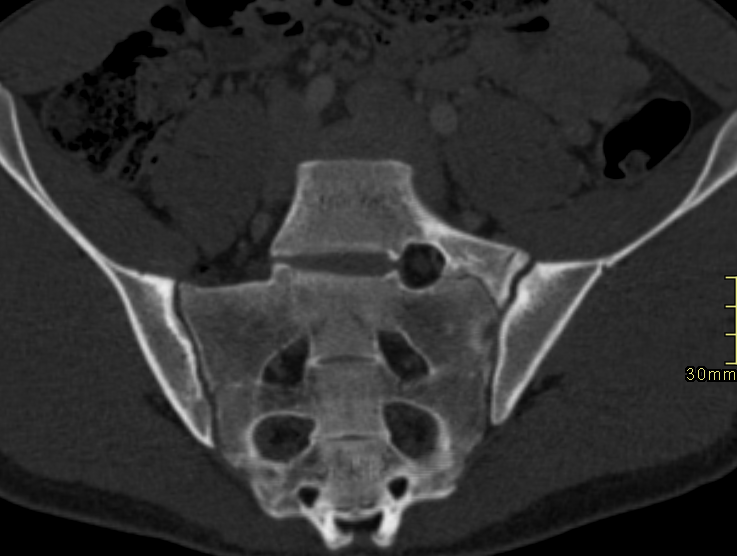

Bertolotti Syndrome